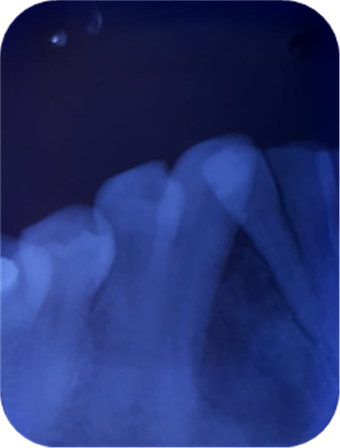

El estudio radiográfico puede evidenciar múltiples sombras radiopacas rodeadas de un halo radiolúcido pertenecientes a un tumor odontogénico CIE10: D164 (odontoma compuesto), localizados en a nivel de los órganos dentarios 4.3; 4.1; 3.1; 3.2; 3.3. También se puede constatar la presencia de una sombra radiopaca que concuerdan con el órgano dentario retenido.

Imagen 2. Radiografica Panorámica.

Imagen 4. Oclusal Inferior.

El diagnóstico y tratamiento oportuno que se debe tener frente a las neoplasias odontogénicas que son frecuentes en la consulta odontológica, y la mayoría de casos pasa desapercibido nos hacen tomar conciencia de lo importante de tratar , guiar a los pacientes que visitan la unidad de atención odontológica Uniandes a realizarse exámenes complementarios, radiográficos panorámicos, periapicales, oclusales que tienen la posibilidad de demostrar una visión más clara de las estructuras dentarias vecinas, previniendo desarrollos o formaciones de neoplasias ya que, las radiografías las intraorales periapicales, oclusales demuestra mayor fidelidad dimensional en comparación a la panorámica detectando oportunamente patologías que son asintomáticas.

En su gran mayoría en la presentación de este caso clínico se puede observar la presencia de una sombra radiopaca que concuerdan con el órgano dentario retenido 4.2.con una imagen mixta con múltiples radiopacidades muy similares a los órganos dentarios que están rodeados de un halo radiolúcido perimetral que son similares descripciones de investigaciones de otros autores.